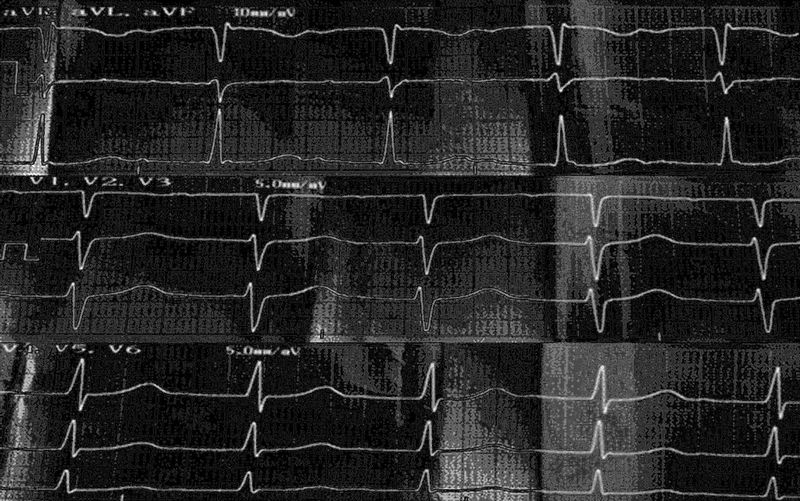

На ЭКГ (рис. 2) — синусовая тахикардия (ЧСС 116 в минуту), АВ-блокада I степени (PQ 0,23 мс).

Рис. 2. Фрагмент (усиленные от конечностей, грудные отведения) электрокардиограммы (скорость записи 50 мс) пациента от 11.04 (13-й день болезни)